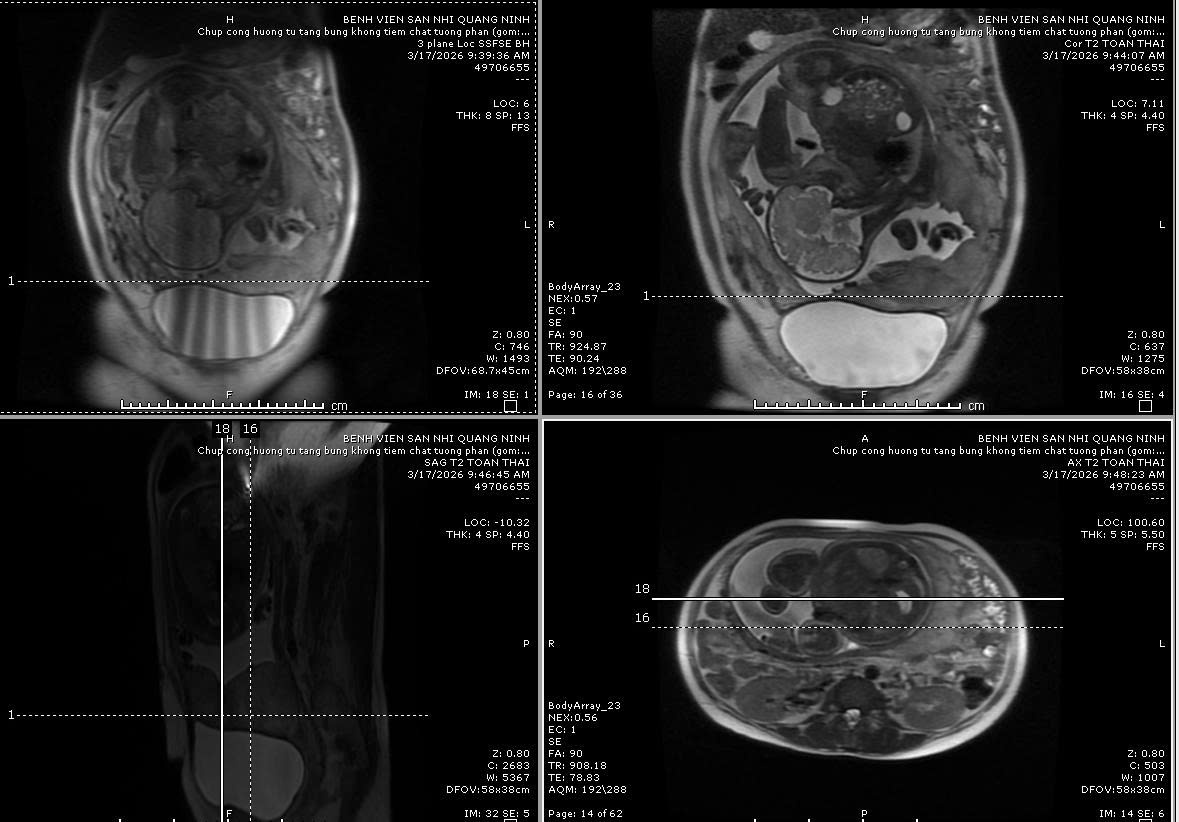

Kết quả siêu âm và chụp cộng hưởng từ cho thấy hình ảnh rau bám mặt trước, mép dưới bánh rau bám lan qua lỗ trong cổ tử cung, có đoạn mất khoảng sáng sau rau, nhiều mạch máu xuyên qua thành cơ tử cung sang phía bàng quang, gây tình trạng chảy máu đột ngột vô cùng nguy hiểm đối với sản phụ và thai nhi.